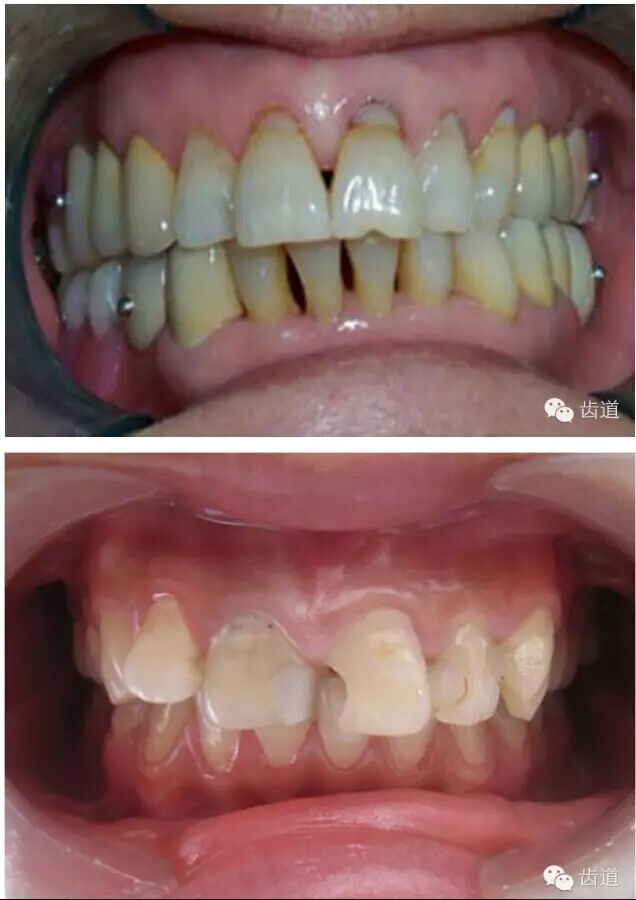

l實(shí)際備牙產(chǎn)生的問題

l防止過度預(yù)備(造成牙髓激惹)

l保留活髓(保留牙體的整體性和韌性)

l過度預(yù)備抗力形喪失